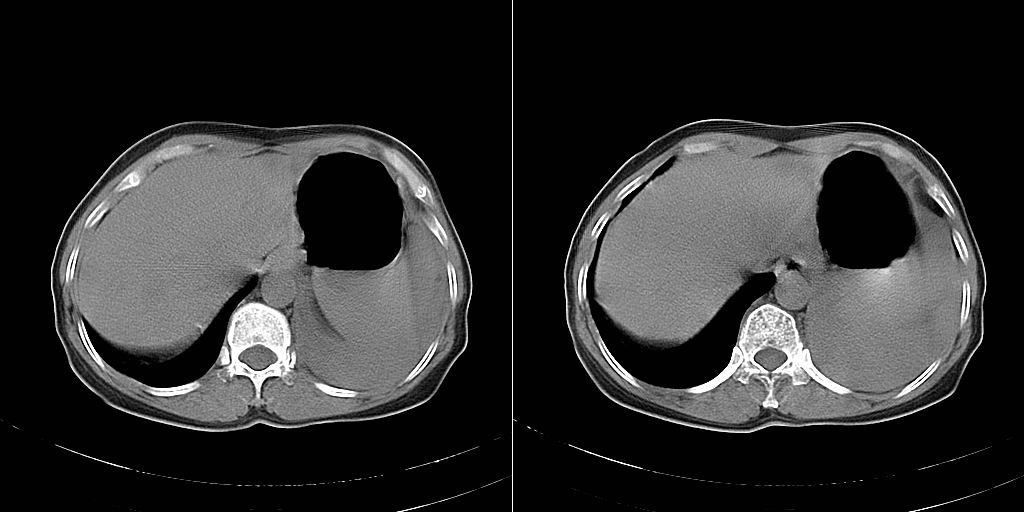

以下是引用dyqct在2007-1-23 15:01:00的发言:[br]左肺下叶实变、略萎陷,近肺门下部密度不均。上腔静脉后及隆突前见肿大淋巴结。余未见异常。[br]考虑:1、左肺下叶中心型肺癌伴肺不张、纵隔淋巴结转移;[br] 2、建议增强扫描并做任意平面重建确定肿块范围及支气管受累情况。

以下是引用同在2007-1-23 19:59:00的发言:[br]左肺下叶中央型肺癌伴肺不张及纵隔淋巴结转移.